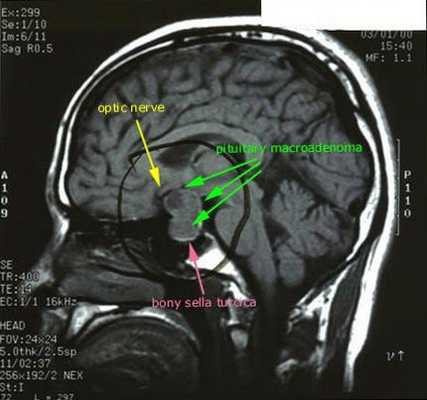

· МРТ головного мозга с контрастным усилением;

После подтверждённого гиперкортицизма необходимо проведение инструментальных методов исследования (МРТ гипофиза, КТ надпочечников).

При БИК в 80-85% случаев выявляют микроаденому гипофиза (опухоль до 10 мм), у остальных 15-20% — макроаденому (доброкачественное новообразование от 10 мм). [7]

- МРТ области турецкого седла с контрастированием

- МРТ области турецкого седла с контрастированием;